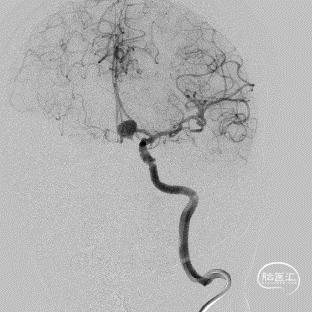

DSA结果:造影发现前交通动脉瘤,3D成像测量直径12mm,载瘤动脉直径1.85mm

术前DSA的正位、侧位造影:

右侧颈内动脉DSA:

术前3D-DSA造影:测量动脉瘤直径在12mm,载瘤动脉直径1.85mm。